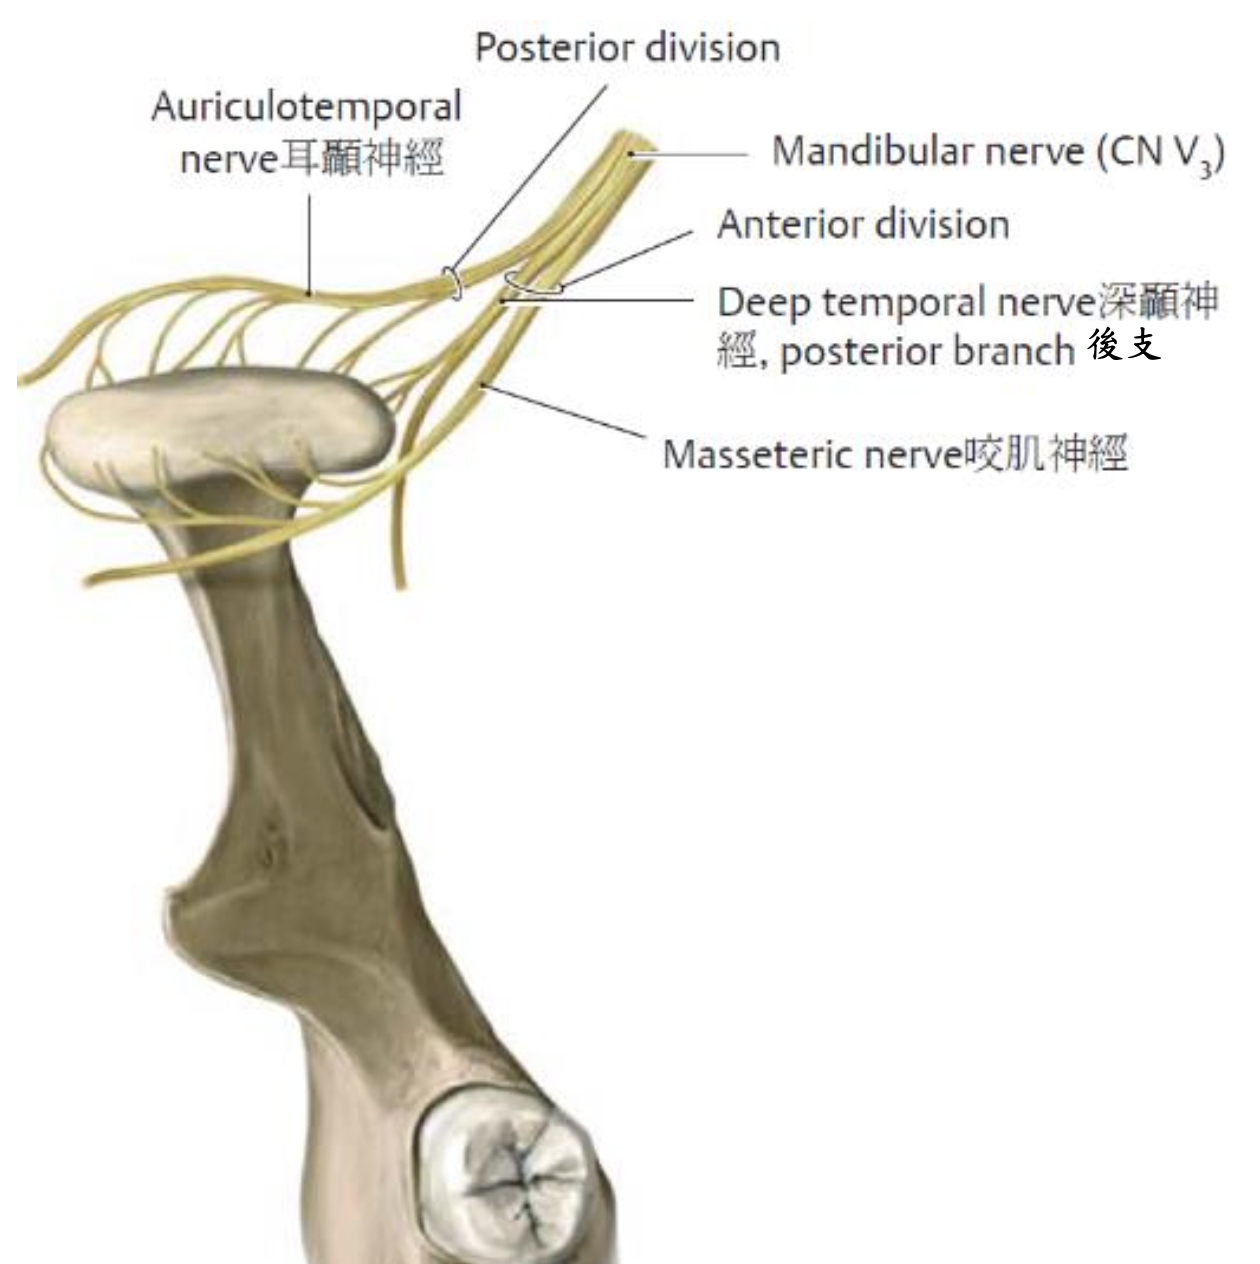

CN V3

Meningeal br.

進入 foramen spinosum

Anterior division

- Masseteric n.

- Anterior and posterior deep temporal n.

- Medial pterygoid n.

- Lateral pterygoid n.

- Buccal n.(Sensory)

Posterior division

- Auriculotemporal n.

- 夾 mid. meningeal a.

- 走進 Digastric, Stylomastoid 之間

- Lingual n.

- Inf. alveolar n.

- Mental n.

- 進入Mandibular foramen

- Incisive n.

- 下顎前牙感覺

- Mental n.

- Mylohyoid n. (Motor)

- Middle meningeal

- 被Auriculotemporal n. 環繞